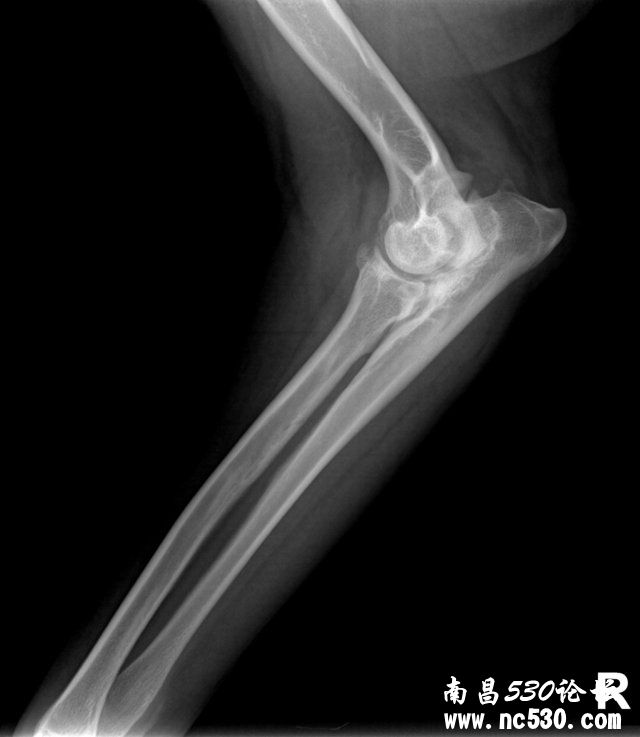

[疾病诊断] 求帮我看下这张肘关节片子是否有问题及严重程度?

求帮我看下这张肘关节片子是否有问题及严重程度?

动物种类:犬

动物品种:拉布拉多

动物年龄:17个月

动物性别:母